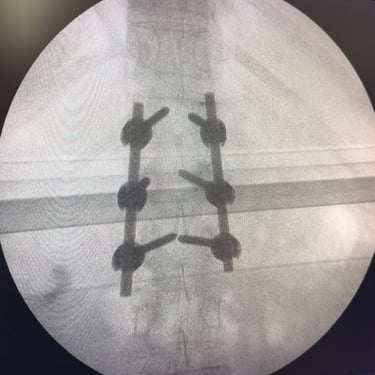

Fractura vertebral lumbar – Artrodesis con tornillos transpediculares (FTP).

La fractura vertebral lumbar es una lesión que puede comprometer la estabilidad de la columna y generar dolor, deformidad o déficit neurológico. En casos seleccionados, el tratamiento quirúrgico mediante artrodesis con tornillos transpediculares (FTP) permite una fijación firme de las vértebras afectadas, restaurando la alineación y brindando estabilidad inmediata. Esta técnica reduce el dolor, previene el desplazamiento vertebral y protege las estructuras neurológicas. La intervención oportuna, junto a una adecuada rehabilitación, favorece una recuperación funcional segura y mejora significativamente la calidad de vida del paciente.